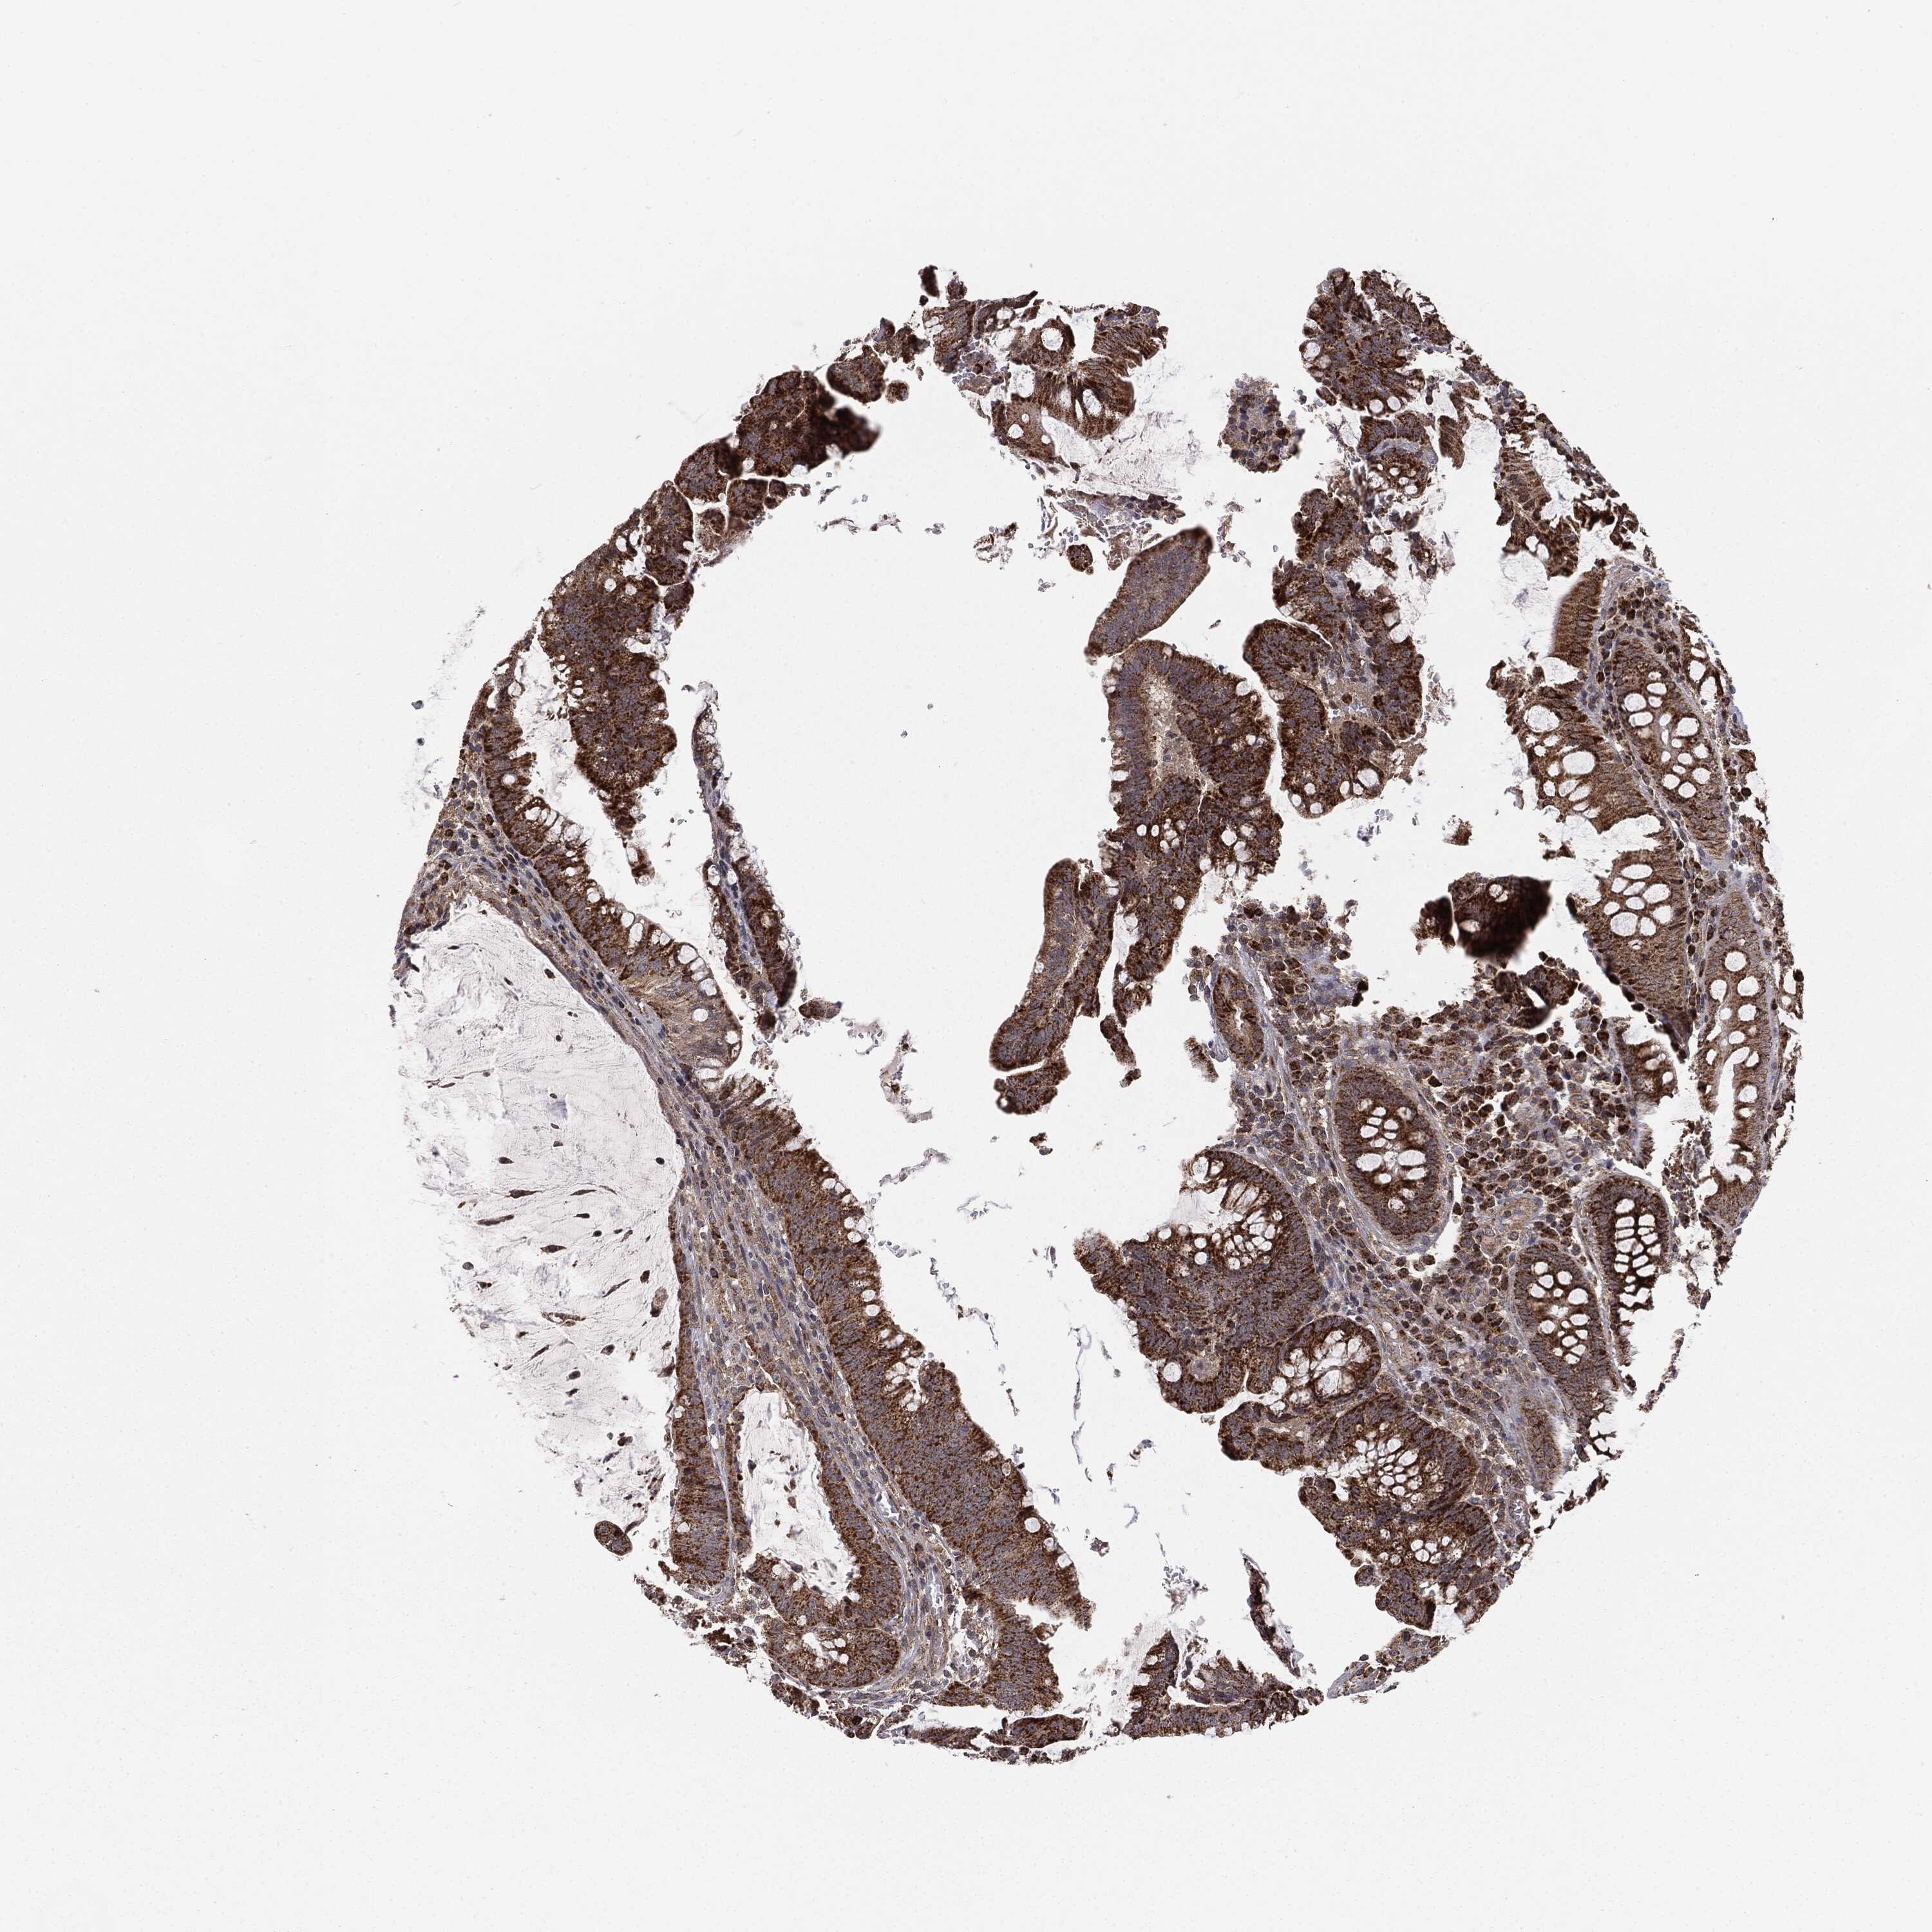

CANCER COLORECTAL CANCER Show tissue menu

ANTIBODIES

AND

VALIDATION